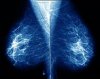

Cancer du sein : la radiothérapie pour les femmes âgées a-t-elle un intérêt ?

Jusqu’à présent on n’avait pas évalué l’intérêt d’ajouter une radiothérapie au traitement par tamoxifène après une tumorectomie chez les femmes âgées. C’est désormais chose faîte grâce à une étude conduite par une équipe américaine sous l'autorité du Dr. Kevin Hughes de l’hôpital général du Massachusetts à Boston. Les résultats de cette étude multicentrique ont été publiés dans la dernière livraison du New England Journal of Medicine.